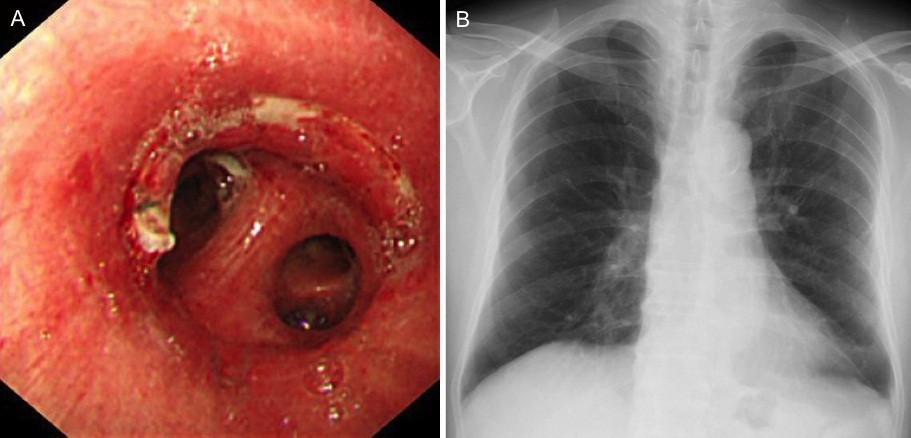

Bronchial Sleeve Resection For Early-stage Squamous Cell Carcinoma

squamous carcinoma resection bronchial